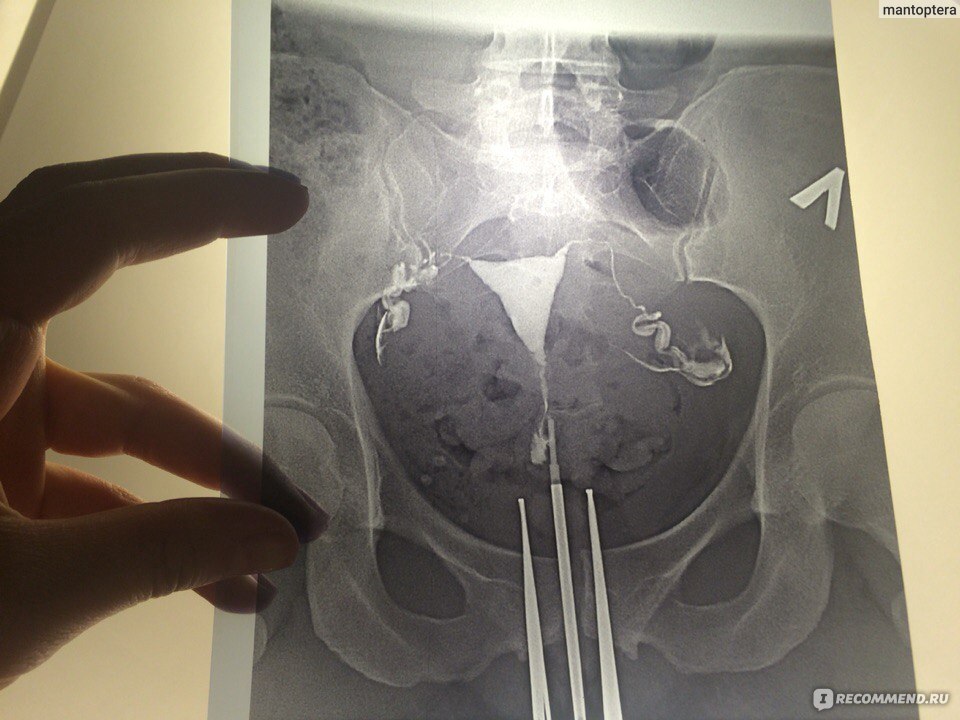

Гистеросальпингография: описание и фотографии